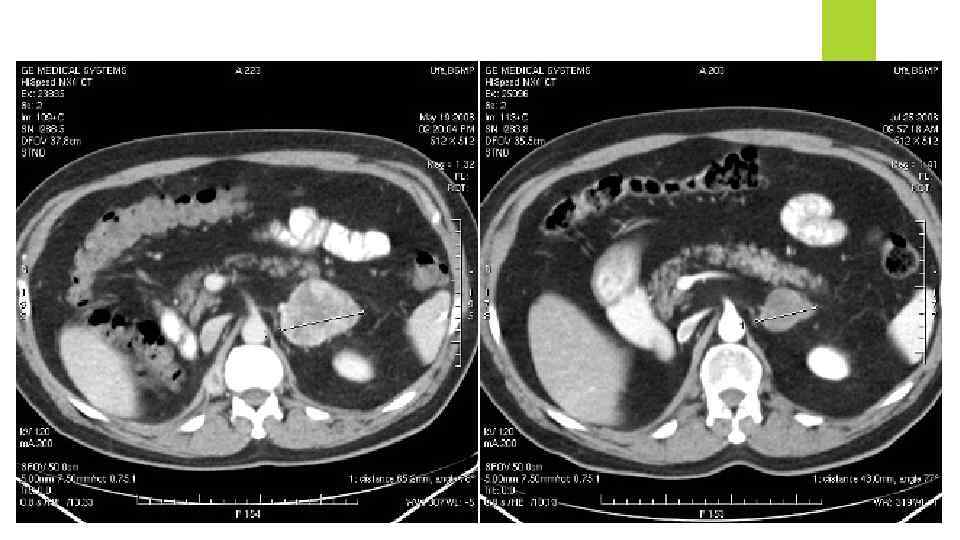

Компьютерная томография: При помощи компьютерного томографа делают снимки не только грудной клетки, но и живота и мозга. Все это делается с целью определить - нет ли метастаз в других органах. Компьютерный томограф более чувствителен к узелкам в легких. Иногда, для более точного обнаружения проблемных мест, в кровь больного вводят контрастные вещества. Само компьютерное сканирования обычно проходит без всяких побочных эффектов, но ввод контрастных веществ иногда вызывает зуд, сыпь и крапивницу. Также как и рентгенография грудной клетка компьютерная томография только находит проблемы места, но не позволяет точно сказать рак это или чтото другое. Для подтверждения ракового диагноза требуются дополнительные исследования.

Компьютерная томография: При помощи компьютерного томографа делают снимки не только грудной клетки, но и живота и мозга. Все это делается с целью определить - нет ли метастаз в других органах. Компьютерный томограф более чувствителен к узелкам в легких. Иногда, для более точного обнаружения проблемных мест, в кровь больного вводят контрастные вещества. Само компьютерное сканирования обычно проходит без всяких побочных эффектов, но ввод контрастных веществ иногда вызывает зуд, сыпь и крапивницу. Также как и рентгенография грудной клетка компьютерная томография только находит проблемы места, но не позволяет точно сказать рак это или чтото другое. Для подтверждения ракового диагноза требуются дополнительные исследования.